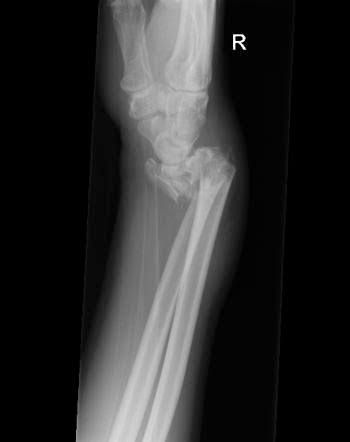

Smith fracture

A Smith fracture is a break to the end of the radius. The end part of the bone, which forms part of the wrist joint, is displaced or angled in the direction of the palm of the hand. Often, this injury occurs by a fall to the back of a flexed wrist but can occur in any fall to an outstretched hand.